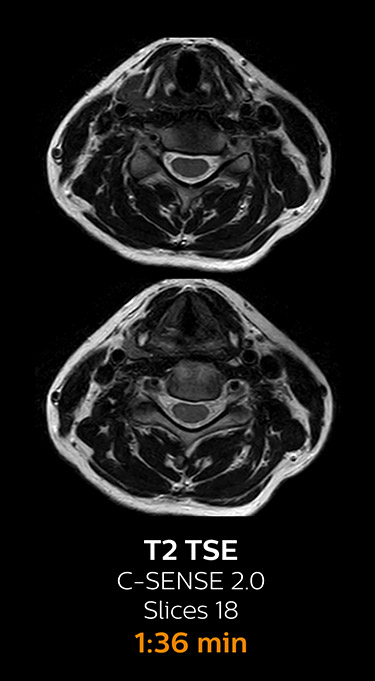

With Compressed SENSE, the scan time for the routine cervical spine examination at KNC was reduced from 13:11 to 9:52 minutes, which corresponds to 25% reduction.

MRI examination of the cervical spine with Compressed SENSE

Ingenia 3.0T CX

Scan time 9:52 min. (was 13:11 min. without Compressed SENSE)